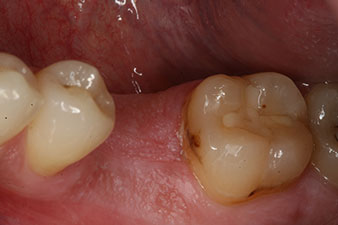

Initial clinical situation

Fig. 1: Initial clinical situation after healing of extraction alveolus 36: The bone base is wide and there is sufficient keratinized gingiva.

A 28-year-old patient with a history of heavy smoking had to have tooth 36 extracted as a result of recurring apical periodontitis.